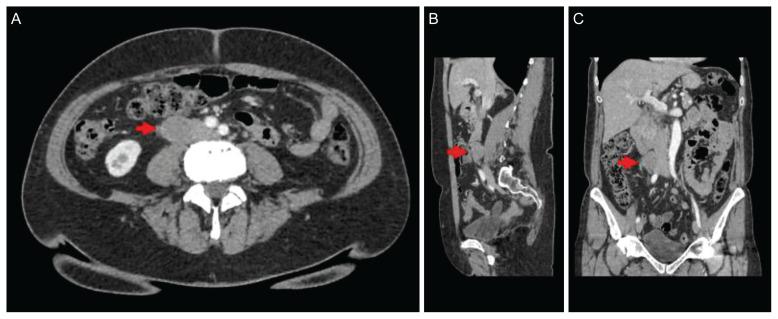

A narrative video demonstration of robotic-assisted surgery to remove recurrent ovarian cancer in a pericaval lymph node. A 62-year-old female presented with recurrent carcinoma of the pericaval lymph node. After 40 months of surveillance, the patient was asymptomatic, but a computed tomography (CT) scan showed an isolated mass (2.7×2.3 cm) in the right pericaval lymph node. Her cancer antigen (CA)-125 level increased from 26 to 46 U/mL. The robotic Xi platform was used to remove the metastatic lymph nodes. The first step was diagnostic laparoscopy. The second step was robotic port placement below the umbilicus. The third step was dissection and identification of landmarks, and the last step was removal of the tumor and closure.

一段关于机器人辅助手术切除腔静脉旁淋巴结复发性卵巢癌的叙述性视频演示。一名62岁女性出现腔静脉旁淋巴结复发性癌。经过40个月的监测,患者无症状,但计算机断层扫描(CT)显示右腔静脉旁淋巴结有一个孤立肿块(2.7×2.3厘米)。她的癌抗原(CA)-125水平从26 U/mL升至46 U/mL。使用达芬奇Xi机器人平台切除转移性淋巴结。第一步是诊断性腹腔镜检查。第二步是在脐下放置机器人端口。第三步是解剖和识别标志,最后一步是切除肿瘤并缝合。